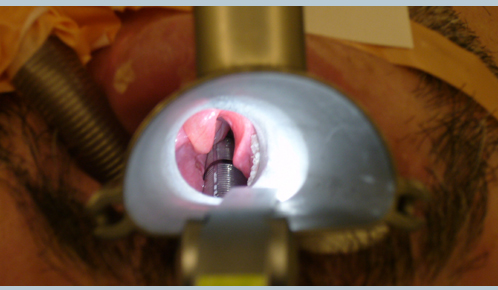

Microdirect Laryngoscopy